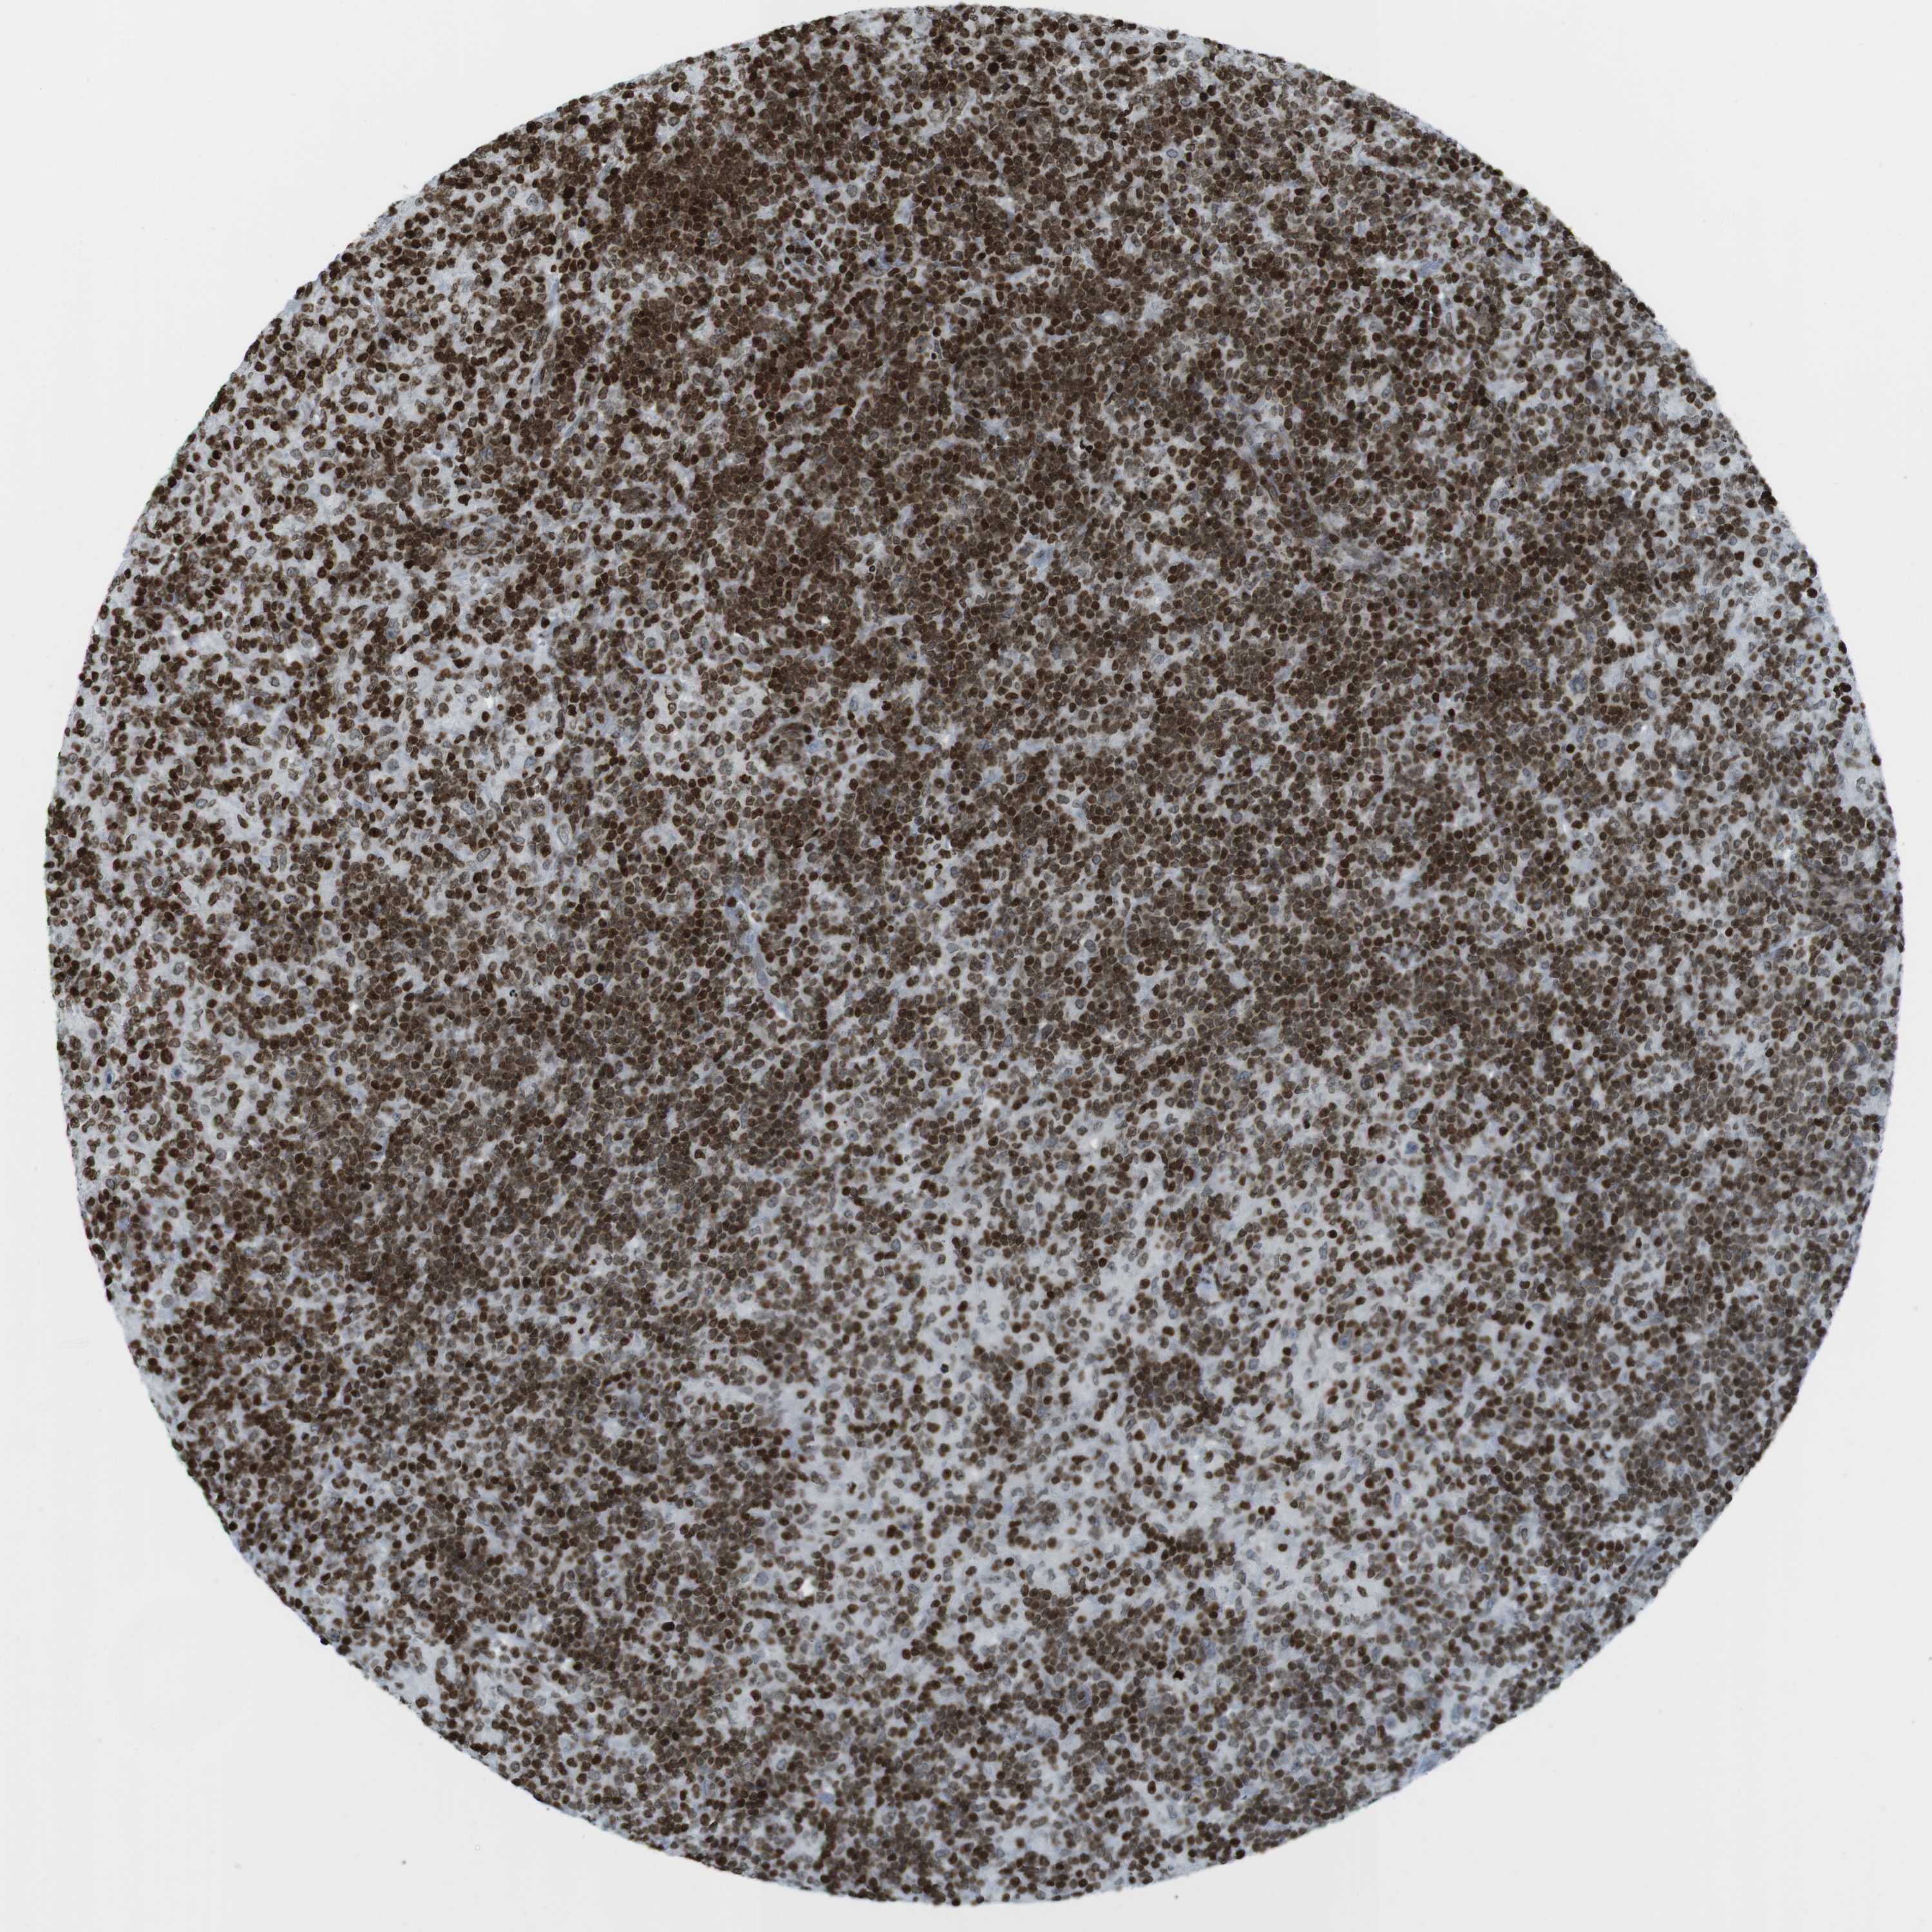

LYMPHOMA - Protein expressioni

A mouse-over function shows sample information and annotation data. Click on an image to view it in a full screen mode. Samples can be filtered based on level of antibody staining by selecting one or several of the following categories: high, medium, low and not detected. The assay and annotation is described here.

Each image is clickable and will lead to virtual microscopy that enables deeper exploration of all samples and also displays staining intensity scores, fraction scores and subcellular localization as well as patient and tissue information for each sample.

Antibody HPA041189

Antibody CAB012242

Staining

High

Medium

Low

Not detected

Intensity

Strong

Moderate

Weak

Negative

Quantity

>75%

75%-25%

<25%

None

Location

Nuclear

Cytoplasmic/membranous

Cytoplasmic/membranous,nuclear

Hodgkin's disease, NOS

Malignant lymphoma, non-Hodgkin's type, High grade

Malignant lymphoma, non-Hodgkin's type, Low grade